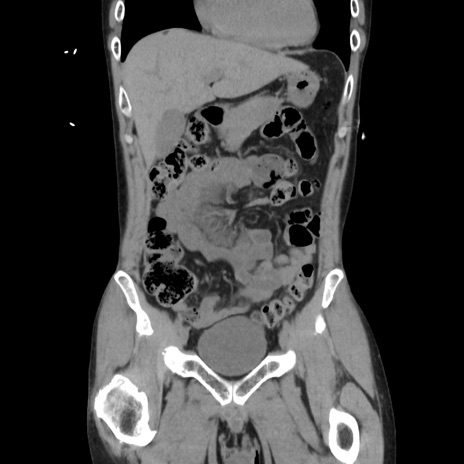

症例37(冠状断像)

【症例】40歳代 男性

【主訴】腹痛

【現病歴】4時間ほど前に電車に乗車中に臍部上より腹痛出現。徐々に増悪し起立困難となり、救急外来受診。生ものは数日食べていない。今朝お雑煮を食べた。

【身体所見】BT 36.8℃、BP 117/84mmHg、HR 91/min、SpO2 97%、苦悶様、腹部:臍上部広範囲圧痛あり、反跳痛±

【データ】WBC 8100、CRP 0.03